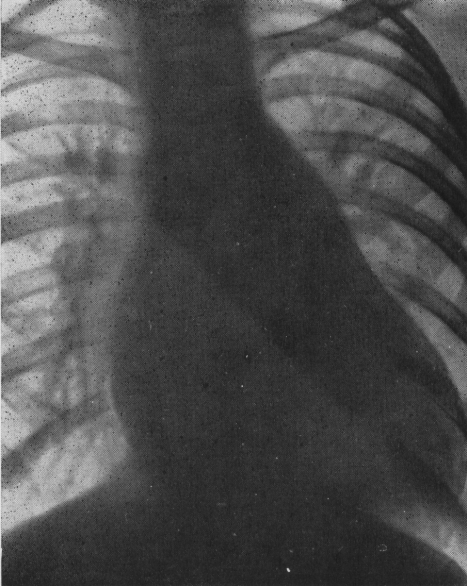

Рентгенологічно: збільшення ЛШ і лівого передсердя, посилення легеневого судинного малюнка, вибухання висхідної аорти, при високій легеневій гіпертензії – збільшення правого шлуночка.

Рис. Дефект міжпередсердної перетинки (значно виражений).

Рентгенологічно: при невеликих ДМШП – норма, при великому “скиданні” крові зліва направо – посилення легеневого судинного малюнка, збільшення лівого шлуночка. При легеневій гіпертензії – виражене збільшення стовбура легеневої артерії з різким звуженням дистальних її гілок.

Рентгенологічно знаходять збільшення правого передсердя і правого шлуночка, розширення легеневої артерії та її гілок, посилення легеневого судинного малюнка; при наявності мітральної недостатності – збільшення лівого передсердя; у випадку аномального впадіння правих легеневих вен в нижню порожнисту вену біля межі правого передсердя з’являється тінь у вигляді “турецької шаблі”.